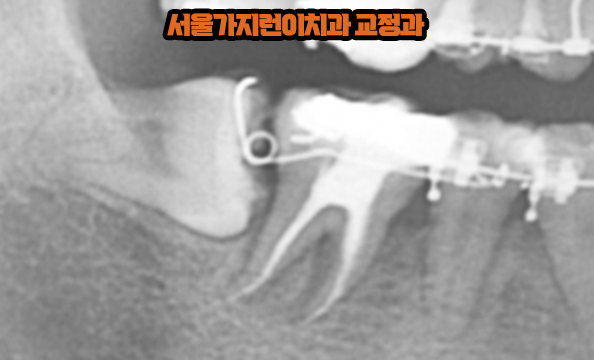

안녕하세요? 서울가지런이치과 교정과 의원입니다. 위 사진은 실제로 저희 치과를 다녀간 환자분의 엑스레이 사진인데요. 보면는 위아래로 사랑니가 나있는 걸 확인할 수 있습니다. 아래의 경우 옆으로 누워있게 났기 때문에 일반적인 치아교정을 했다고 한다면 발치하고 교정을 진행했겠죠. 하지만 사랑니의 모양도 양호한데다 똑바로 세우게 된다면 어금니 역할을 충분히 할 수 있다고 판단이 되었기 때문에 임플란트 대신 치아교정을 통해 구강저작력을 높여볼 수 있었습니다.

네, 가능합니다. 위 사진은 사랑니를 당겨오는 과정인데요. 임플란트와 달리 사랑니는 자연치아기 때문에 치주인대가 일종의 쿠션역할을 해서 저작시 발생하는 충격을 완화해주는데다 지속적으로 힘을 주면 치아이동이 가능하기 때문에 어금니 결손을 해소할 수 있었습니다. 또 사랑니 모습을 보면 보철치료가 들어간 것을 확인할 수 있는데요. 모든 보철치료가 그런 것은 아니지만 치아 위에 씌우는 보철치료후에는 치아교정이 어려울 수 있으니 꼭 치아 손상치료를 하기 전에 교정상담부터 받아보는 걸 권유드립니다.

서울가지런이치과 교정과 의원의 대표원장님께서는 90도로 쓰러진 매복사랑니케이스로 만족스러운 임상결과를 얻을 수 있다는 강의를 진행한 바 있었는데요. 해당 연구는 그 기여도를 인정받아 감사장을 수여받기도 했습니다. 그만큼 효과와 안정성을 인정받은 것인데요. 전체적인 치열을 다듬으면서 사랑니를 세우게 되면 얼마간의 기간이 지나 아래처럼 어금니로 완전히 자리 잡은 모습을 확인할 수 있게 됩니다.